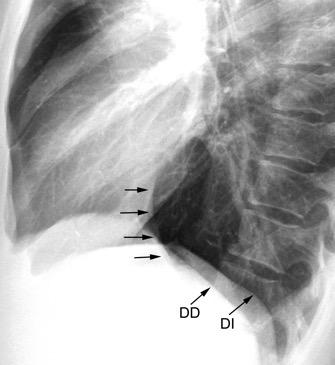

Líneas paraespinales formando un “paréntesis” por encima del diafragma. El signo señala el origen “intratorácico” de la lesión.

Conrad A et al. Pott’s disease associated with large and multiple abscesses in a 30-year-old migrant from Chad. BMJ Case Rep 2018

(lesiones toracoabdominales) La divergencia de las líneas paraespinales apunta a lesión toracoabdominal, que desde el tórax desciende y penetra en el abdomen.

Signo del “iceberg” positivo en Tb vertebral

Afectación por vía hematógena. Región dorsolumbar más frecuente. Afectación inicial: irregularidad de los platillos vertebrales, disminución del disco intervertebral con esclerosis ósea adyacente. Kim. Radiographics.2001